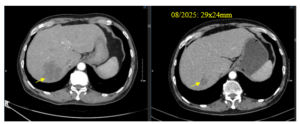

CASE LÂM SÀNG: U Thần kinh nội tiết tế bào lớn biểu hiện tại gan

CASE LÂM SÀNG U Thần kinh nội tiết tế bào lớn biểu hiện tại gan GS. TS. Mai Trọng Khoa, PGS. TS. Phạm Cẩm phương, PGS. TS. Phạm Văn Thái, ThS. BSNT. Hoàng Công Tùng, SV. Lê Thu Hương 1. Trung tâm Y học hạt nhân và Ung bướu, Bệnh...